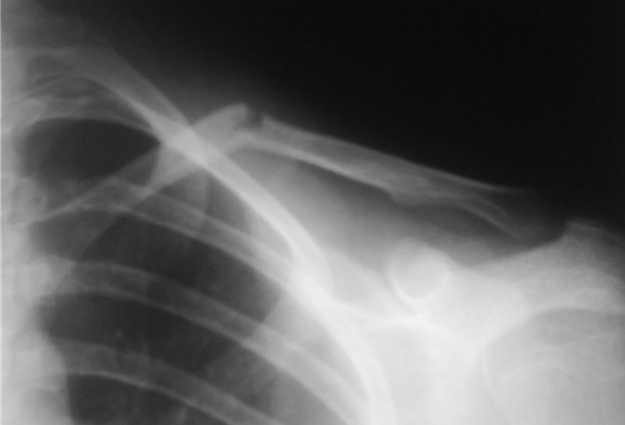

На следующий день, родители привели девочку с жалобами на давление в

левом надплечье и онемение правого предплечья и 1,2, 3-го пальцев

кисти.

Мной была немедленно снята наложенная накануне повязка, и заменена на

марлевую Дезо. 09-07-го, Дезо заменена на "косыночную" повязку

Сегодня произведен контрольный снимок.

На сегодняшний день сохраняется онемение 1-3 пальцев.